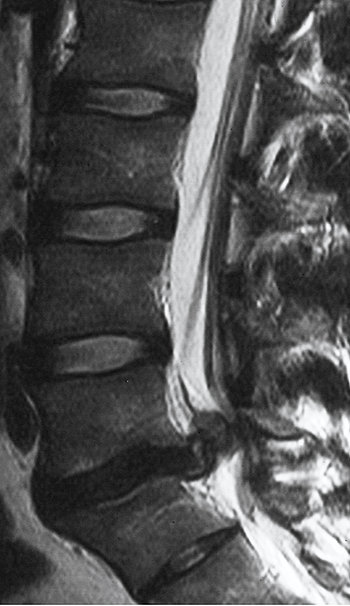

A herniated disc is a spine condition that occurs . when the gel. Sometimes the herniation is so severe that a free fragment occurs, meaning a piece has broken completely free from the disc and is in the spinal canal. Herniated Cervical Disc . ... Access Content

Posterior Epidural Migration of a Sequestrated Lumbar Disk Fragment: MR Imaging Findings C.Y. Chen Manz HJ, Vidic B, et al. Disc fragment migration. Radiology 1990;175:831 36 2. DosogluM,IsM,GezenF,etal Atypical lumbar disc herniation: a case report. Spine J 2002;2:224 26 ... Doc Viewer

Spontaneous Regression Of Posterior Epidural Migrated Lumbar ...

A sequestered disc fragment, or free fragment, as it is sometimes called, Disc Herniation Types 3. What Is Radiculopathy? 4. Diagnosing Cervical Radiculopathy 5. What is Discogenic Pain? About.com; About Health; Back & Neck Pain. . . ... Read Article